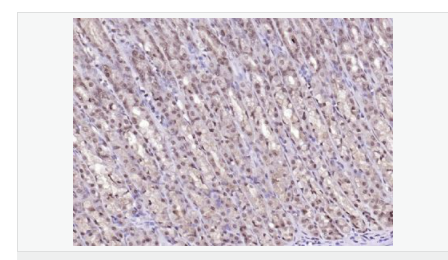

| 英文名稱(chēng) | LSM3 |

| 中文名稱(chēng) | LSM3蛋白抗體 |

| 別 名 | lsm3; LSM3 homolog; LSM3 protein; LSM3_HUMAN; MDS017; SMX4; U6 small nuclear RNA associated (S. cerevisiae); U6 snRNA associated Sm like protein LSm3; U6 snRNA-associated Sm-like protein LSm3; USS2; YLR438C. |

| 研究領(lǐng)域 | 細胞生物 結合蛋白 表觀(guān)遺傳學(xué) |

| 產(chǎn)品應用 | WB=1:500-2000 ELISA=1:5000-10000 IHC-P=1:100-500 IHC-F=1:100-500 ICC=1:100-500 IF=1:100-500 (石蠟切片需做抗原修復) not yet tested in other applications. optimal dilutions/concentrations should be determined by the end user. |

| 細胞定位 | 細胞核 |

| 產(chǎn)品介紹 | Sm-like proteins were identified in a variety of organisms based on sequence homology with the Sm protein family (see SNRPD2; MIM 601061). Sm-like proteins contain the Sm sequence motif, which consists of 2 regions separated by a linker of variable length that folds as a loop. The Sm-like proteins are thought to form a stable heteromer present in tri-snRNP particles, which are important for pre-mRNA splicing.[supplied by OMIM, Apr 2004] Function: Binds specifically to the 3'-terminal U-tract of U6 snRNA. Subcellular Location: Nucleus. Similarity: Belongs to the snRNP Sm proteins family. SWISS: P62310 Gene ID: 27258 Database links: Entrez Gene: 27258 Human Omim: 607283 Human SwissProt: P62310 Human Unigene: 111632 Human Important Note: This product as supplied is intended for research use only, not for use in human, therapeutic or diagnostic applications. |